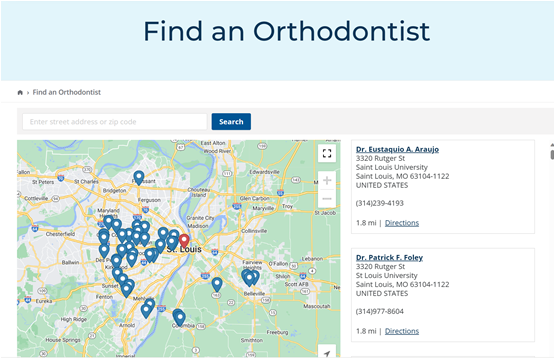

According to statistics, OSA is very prevalent, affecting about 34% of men and 17% of women aged 30-70 years. Due to the inconvenience of the use of positive pressure respirators, the effectiveness and convenience of oral devices can popularize the treatment of OSA. As a result, the C4 airway correction system has a large market to be developed. According to the "Overview of China's Oral Medical Service Market", in 2019, there were 885 dental specialties and about 7,000 dental departments in China(Including 6,287 secondary and tertiary general hospitals, 74 tertiary integrated traditional Chinese and Western medicine hospitals, 450 beauty hospitals, and 141 children's hospitals); National Medical Institution Inquiry System of the National Health Commission, As of December 24, 2020, there are 71,397 oral (dental) clinics nationwide. These hospitals or clinics will be the base for the promotion of the C4 airway correction system.

The market positioning of respiratory orthodontic systems is mainly aimed at those patients with snoring and obstructive sleep apnea (OSA), This is especially true in people who have difficulty or are unable to use positive pressure respirators. The advent of such devices offers an alternative that is more suitable for them, aimed at improving their breathing problems and sleep quality.

On the other hand, dentists are important partners in the respiratory orthodontic system due to their advantages in the diagnosis and treatment of obstructive sleep apnea, as well as their use of specialized equipment such as cone beam computed tomography (CBCT).

In China, the size of the oral medical services market is quite large. According to statistics, in 2019, there were 885 dental hospitals and about 7,000 dental departments in hospitals, and by December 24, 2020, there were 71,397 oral (dental) clinics/outpatient departments nationwide. These establishments could serve as a base for the promotion and sale of the SNOSA respiratory system.